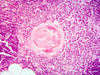

Hassall’s body in Thymus